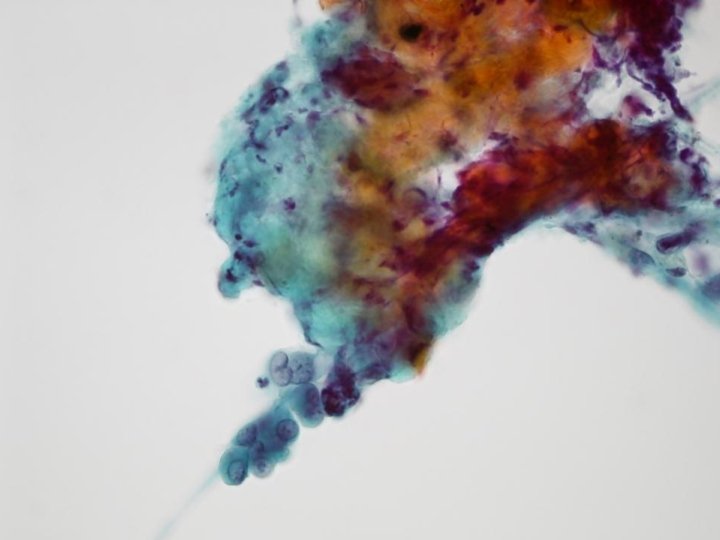

Microscopical features • Paucicellular aspirate • Small and large loosely cohesive cell groups of round to polygonal epithelioid cells • Focally, Papillary or acinar –like structures • Intermediate to large cells, with round to oval nuclei with frequent binucleation and multinucleation • Folded or wrinkled nuclear membrane • Abundant cytoplasm • Eccentrically placed nuclei (plasmacytoid) and granular chromatin with small nucleoli • Intracytoplasmic vacuoles and intranuclear pseudoinclusion • Connective tissue fragment • Lacks necrosis or mitotic figures • Foamy histiocytes and lymphocytes in background